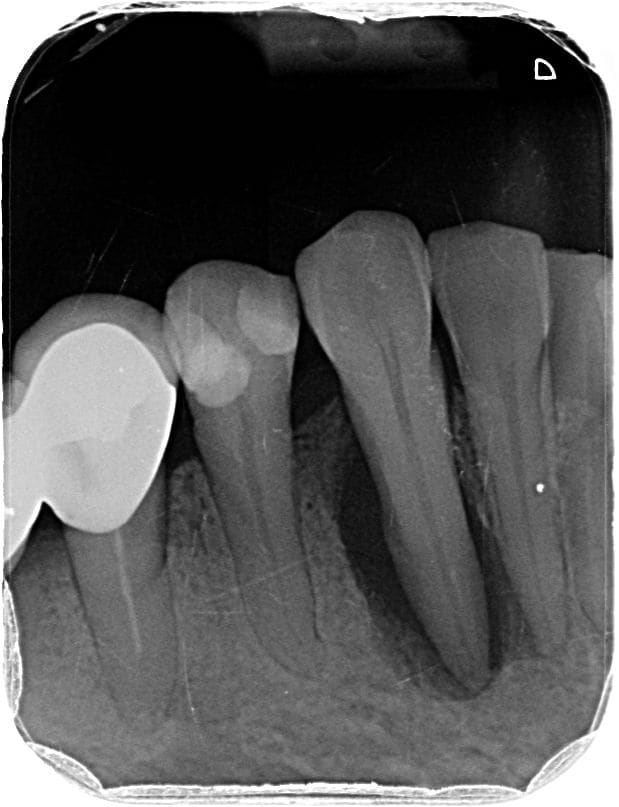

J'aimerais votre avis pour ce cas. Je suis sûre à 99% qu'il faille dévitaliser la 37 suite à pour moi un abcès apical aigu mais je ne trouve pas de réelle cause et j'aimerais savoir si vous aviez une idée.

09/06 : 37 a eu petite gene dernierement a la mastication très léger par moment. Tartre ++ en occlusal de 27 je pense à une sur sollicitation. Elargissement desmodontal sur la radio mais froid positif donc surement traumatique par surocclusion? Si perdure peut etre fracture? A ré évaluer.

07/07 37 : douleur type abcès apical aigu il y a 2 semaines calmées par les ATB. // Scan pour recherche origine fracture, RAS. Test au froid clairement négatif cette fois (on en a reparlé il lui semble vraiment qu'elle sentait le froid la fois d'avant... ) Mobilité 2 de la dent. Plus de tartre antagoniste. La patiente rapporte beaucoup bruxer, on fait donc une gouttière.

Elle est necrosee ca se voit sur la pano à l apex

Il n y a pas 500 possibilités il n y a pas de carie pas de fracture car pas d image en doigt de gant et de signe clinique de fracture ... il reste a mon humble avis que des surcharges de forces peut etre légères et répétées antérieures car pas de surocc a priori

Probable trauma, violent ou modéré mais chronique, ayant entrainé fêlure puis nécrose.

Je confirme l'avis de Thierry, les fêlures ne se voient souvent pas, pas plus à la radio 3D d'ailleurs.

Si test au froid négatif, l'image à la radio ne fait aucun doute: c'est nécrosé, faut dévitaliser.

J'ai constaté qu'avec cette morphologie de racine pour les 7 mandibulaires on avait un risque accru de fêlures fractures.

Problème de répartition des forces, s'il faut deux racines ce n'est pas par hasard, la nature est économe.